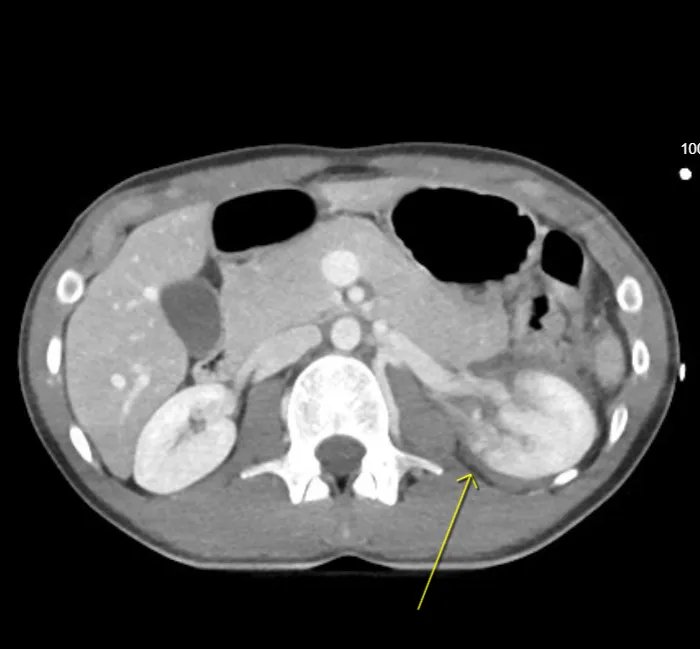

CT is the gold standard for both diagnosis and grading of renal injury. It defines parenchymal lacerations, vascular involvement, collecting-system disruption, and urinary extravasation with high accuracy.

3. Nephrographic phase (80–100 s) – Characterizes parenchymal lacerations, infarcts, and hematomas.

• Lacerations: Linear or branching low-attenuation defects extending from cortex inward.

• Segmental infarction: Wedge-shaped non-enhancing region due to vascular occlusion.

• Vascular pedicle injury: Abrupt arterial cutoff or non-enhancement.

• Active hemorrhage: High-density jet of contrast on dynamic phases.